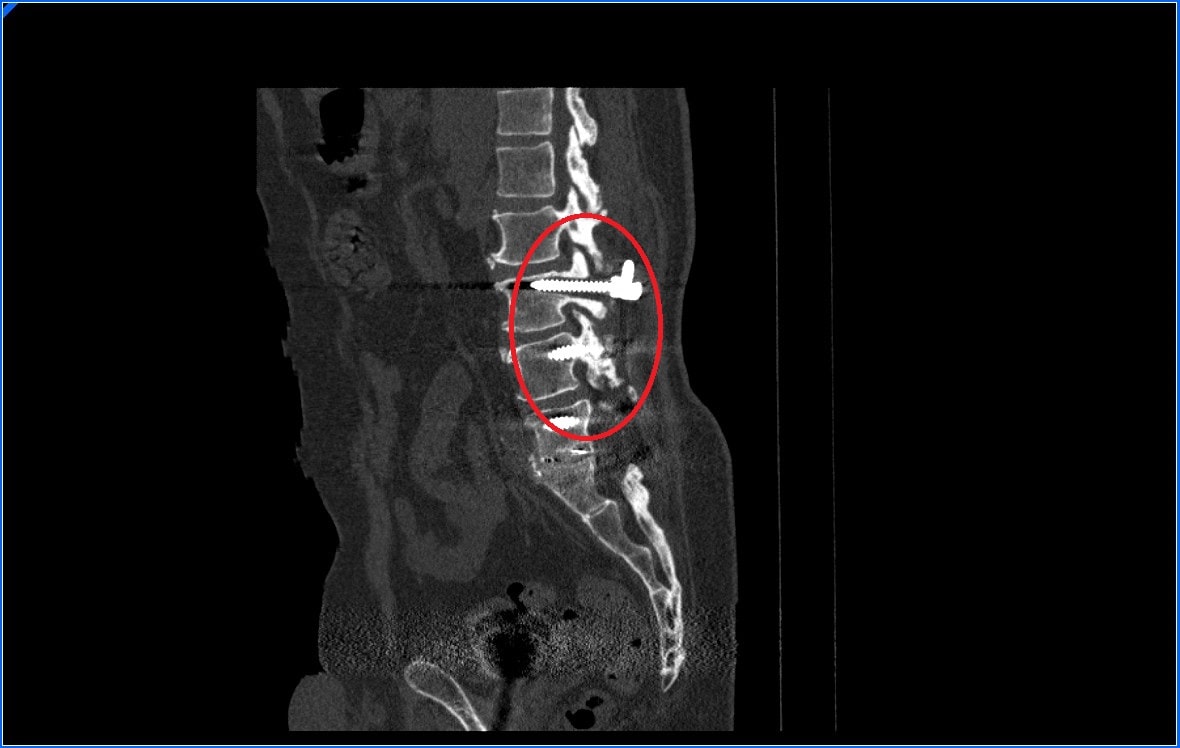

- Arrancamiento de los tornillos. Como ya sabes para realizar una fusión vertebral la mayoría de las veces se utilizan tornillos para impedir que las vértebras se muevan y se fusionen. Si ponemos los tornillos sobre un hueso poco resistente estos se pueden arrancar y soltarse de la vértebra provocando dolor y la necesidad de realizar una re-intervención quirúrgica. Es lo que se conoce como pull-out de los tornillos

- Tornillos cementados. Los tornillos cementados son unos tornillos que permiten introducir cemento a su través. Estos tornillos tienen nos agujeros en la punta a través de los cuales el cemento puede salir. Al endurecerse el cemento, esté sujeta el tornillo y disminuyen las posibilidades de que este tornillos se mueva. La cementación de tornillos sin embargo dificulta una posible cirugía de revisión ya que es complicado retirar los tornillos y en ocasiones queda cemento en el interior de la vértebra dificultando el volver a poner tornillos en esa vértebra.

- Tornillos expansibles. Los tornillos expansibles es el último intento por tratar de aumentar el agarre de los tornillos en la vértebra. Estos tornillos tienen la capacidad de aumentar su diámetro una vez introducidos en la vértebra. De este modo se ajustan mejor y aumenta su sujeción a la vértebra.